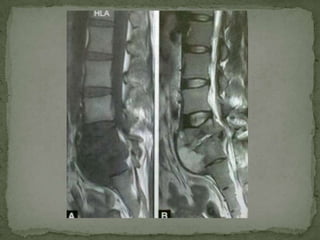

 T1 - usually decreased marrow signal & loss of cortical

definition

 T2 - a relative increase in signal intensity within involved

vertebral bodies and disks

 Disk involvement has been reported in 46 to 72 % of cases

and occurs relatively late compared to pyogenic spondylitis

 ‘Floating disk sign’ - Occasionally the disk space is

preserved despite extensive bone destruction

Paraspinal soft tissue masses / abscesses -

 about 71 % of cases on MRI

 On T1W

 loss of the uniform psoas muscle signal intensity

 enlargement of the affected muscle

 On T2W - hyperintensities

 Postcontrast –

 Thick rim enhancement around intra-osseous and paraspinal

soft tissue abscesses

 More uniform enhancement is seen with granulation tissue

or phlegmon

Epidural extension -

 about 61 % cases on MRI

 displace the thecal sac

 spinal cord is distorted

 Post-contrast fat sat T1W sequences –

 best to demonstrate meningeal and epidural inflammatory

soft tissues,

 with improved definition of cord and nerve root compromise

 Heavily T2W FSE sequences can also be used to provide a

myelographic effect showing thecal sac compression.